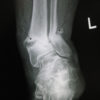

Limited research into electromagnetic and ultrasound bone stimulation devices complicates efforts to determine efficacy. For the majority of people, lower-limb fractures and fractures in other parts of the body heal well and reliably. However, some people experience complications that may cause significant harm.